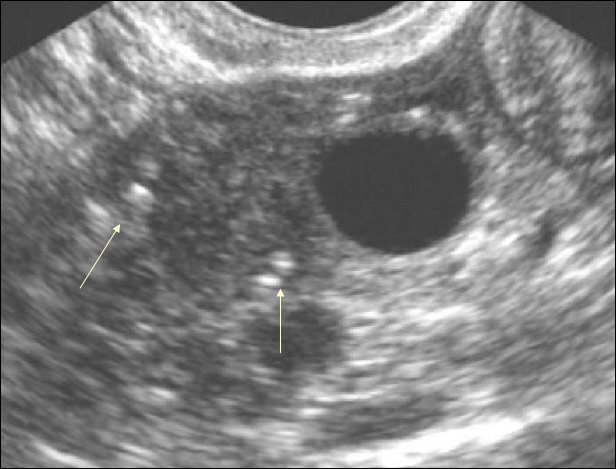

- ультразвуковое исследование;